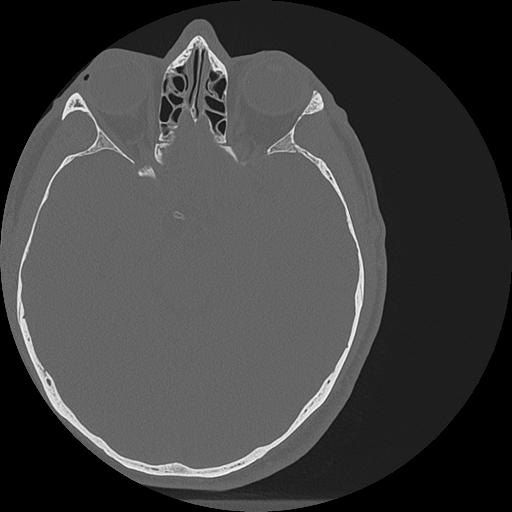

7 HUESO,,Vol,0.5,HUESO,,